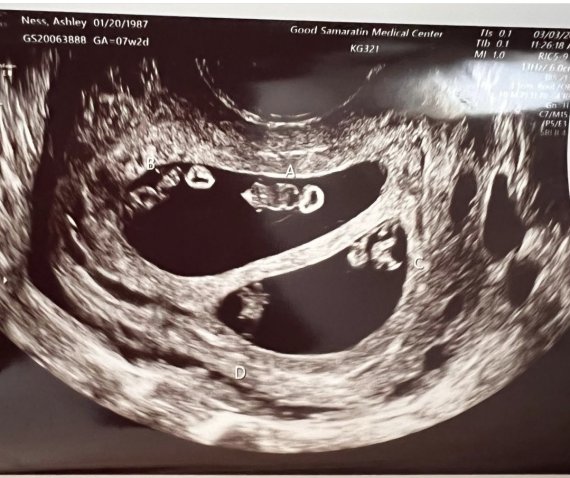

[서울=뉴시스] 미국 매사추세추주에 사는 애슐리 네드는 한 번에 2쌍의 쌍둥이를 임신했다는 소식을 듣고 매우 큰 충격을 받았다. 사진은 그의 초음파 사진. (사진=애슐리 네드 인스타그램 캡처) 2022.06.30. *재판매 및 DB 금지

이 소식을 처음 들었을 땐 매우 기뻤지만 애슐리는 2주 후 초음파 검사를 받고 매우 큰 충격을 받았다. 그가 한 명이 아니라 4명의 아이를 임신했기 때문이다.

심지어 그가 임신한 것은 네 쌍둥이가 아닌 2쌍의 일란성 쌍둥이였다.

의사는 애슐리가 딸 2명과 아들 2명을 임신했다고 말했다. "자연임신으로 2쌍의 쌍둥이를 동시에 임신하는 것은 7000만분의 1의 확률"이라며 놀라워했다.